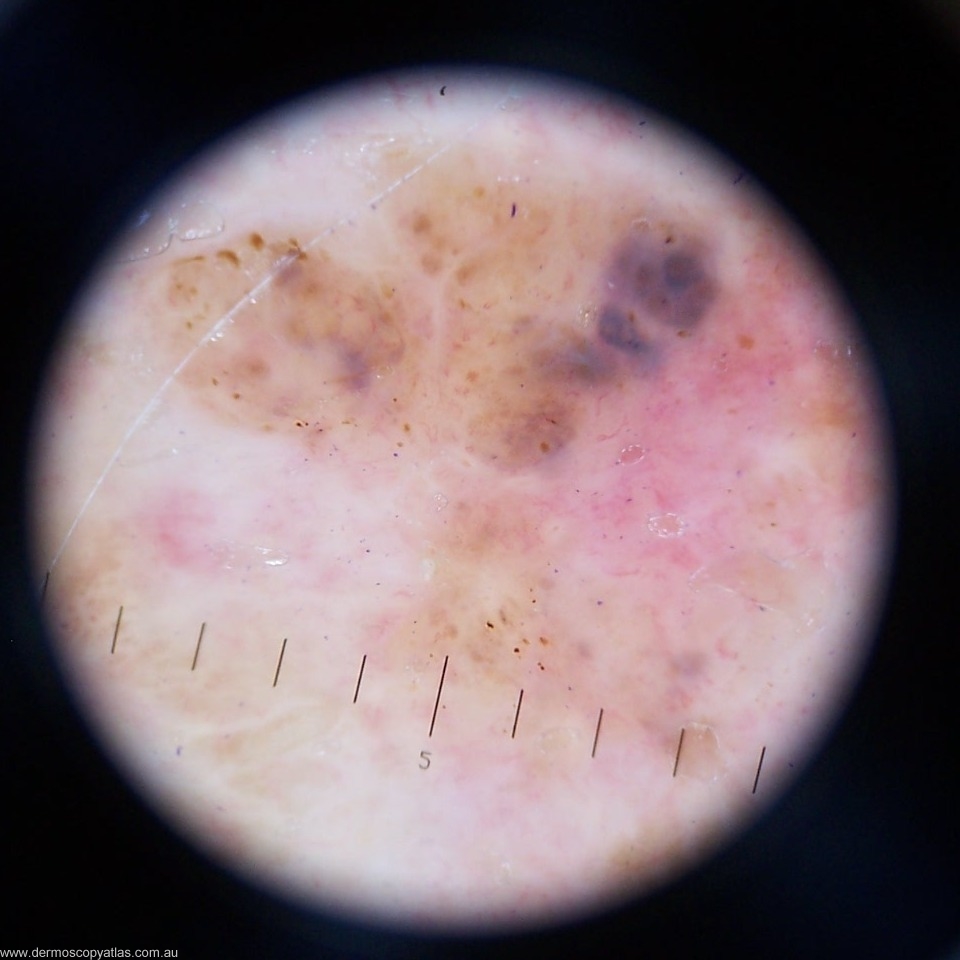

Case 3. This 79 year old patient with type 1 skin has had > 100 NMSC. This apparently new lesion on the anterior shoulder was noted at a 6 monthly check. Consider Solar lentigo, Seborrhoeic keratosis, Pigmented BCC, Nevus, Melanoma or Other.

Answer: Clinically this looks suspicious. It is a pigmented lesion with varying colours and a suggestion of regression.

Answer: There is no obvious network but the brown dots make it melanocytic. The amorphous blue area is suggestive of BCC but the adjacent pink area would be more likely in melanoma. The linear irregular vessels more support melanoma.

Answer: Histology showed " Sections show a superficial spreading malignant melanoma. The lesion is mostly in situ but does include a component which is Level 3 and 0.9 mm thick. Rare dermal mitotic figures are seen (less than 3 per square mm). No ulceration, regr